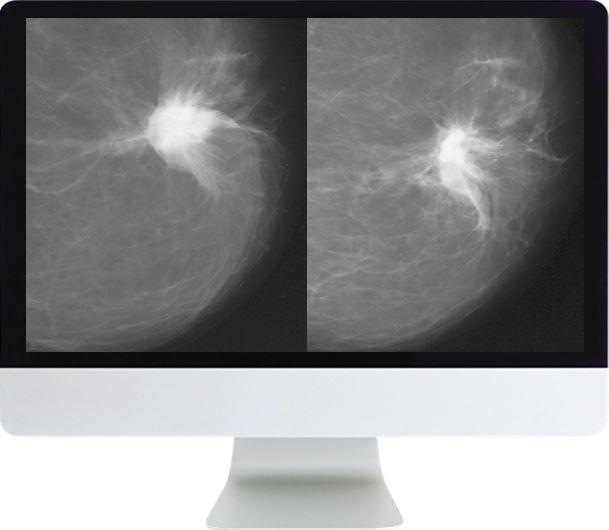

This course will describe the state of various mammographic screening guidelines for women of average risk, review the evidence in peer-reviewed literature, propose uniform metrics for screening mammography, and identify solutions such as risk stratification tools. This course combines the Screening Mammography Debate held in Washington D.C. with 7 AJR articles to provide a comprehensive overview of the arguments currently being debated in screening mammography. The AJR articles that are part of this course are not available for credit anywhere else.

- Screening Mammography in Women 40-49 Years Old: Current Evidence